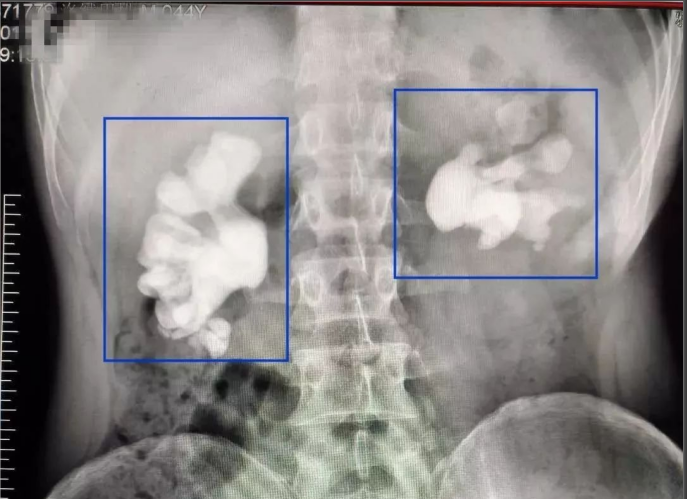

進(jìn)一步通過X線照片檢查發(fā)現(xiàn)雙腎鑄型結(jié)石,右腎盂內(nèi)有大小約11厘米的結(jié)石,其形狀如同“老生姜”,整個右腎盂和所有腎盞腔隙都被結(jié)石填滿,左側(cè)并有嚴(yán)重積液及泌尿道感染?;颊叩淖髠?cè)腎臟腎功能所剩無幾,更為嚴(yán)重的是化驗(yàn)結(jié)果顯示患者總體腎功能已出現(xiàn)衰竭,臨床上已出現(xiàn)輕度貧血等腎衰竭的癥狀,如不及時診治,病人不可避免的要發(fā)展成為尿毒癥,后果非常嚴(yán)重!

腎結(jié)石,鑄狀結(jié)石

雙腎鑄狀結(jié)石